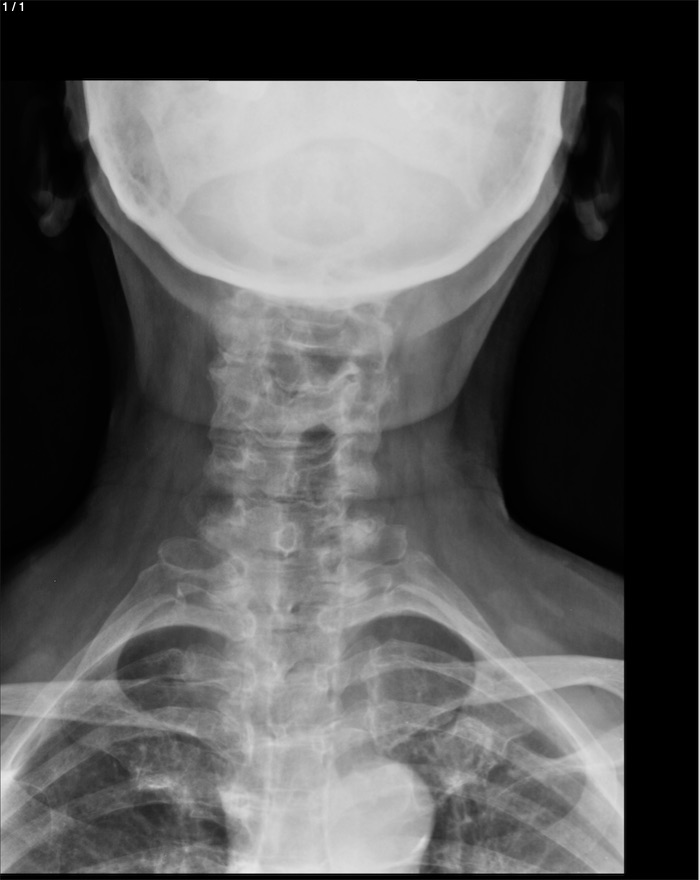

America Farfan Flores - Unnamed